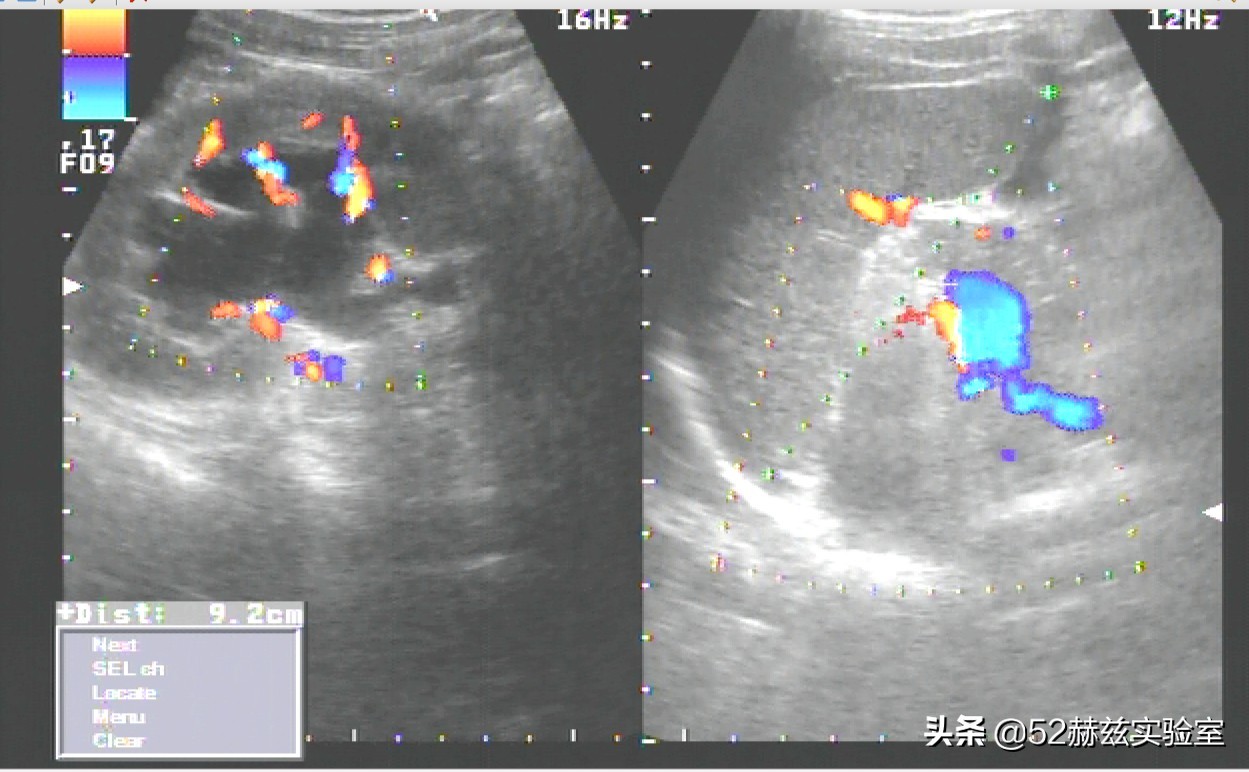

超声刀虽然叫刀,但是肯定和我们日常见到的刀具不一样。严格来说,它并不是真的刀,而是一种高能量聚焦超声仪器。

一样的道理,我们可以利用超声波在生物组织内的方向性、穿透性和可聚焦性等物理特性,将体外能量超声波穿透正常组织,精准聚焦超声波到体内,对需要手术的部位进行相关治疗工作。

医用上它可以用于除骨组织和输卵管之外的所有的人体组织的切割,比如切除人体软组织的肿瘤,粉碎了的肿瘤组织碎屑随时被冲洗并吸出,最神奇的是,手术部位周围的血管神经等却不易损伤。

因此医用超声刀又被称为"超声切割止血刀"。